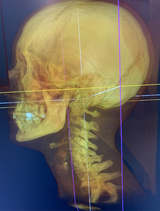

I-CAT Next Gen/FLX delivers an adjustable, large field of view (FOV) cone beam scan up to 17 x 23 cm for the widest range of applications. Advanced features include 3D reconstructions and a fast scan protocol to minimize patient exposure.

Improved Diagnostic Accuracy: CBCT provides three-dimensional (3D) images of the patient's anatomy, allowing for more accurate and detailed assessments of the area of interest.

Improved Patient Communication: The 3D images generated by CBCT are easier for patients to understand and visualize, facilitating communication between the clinician and the patient regarding their condition and treatment options.